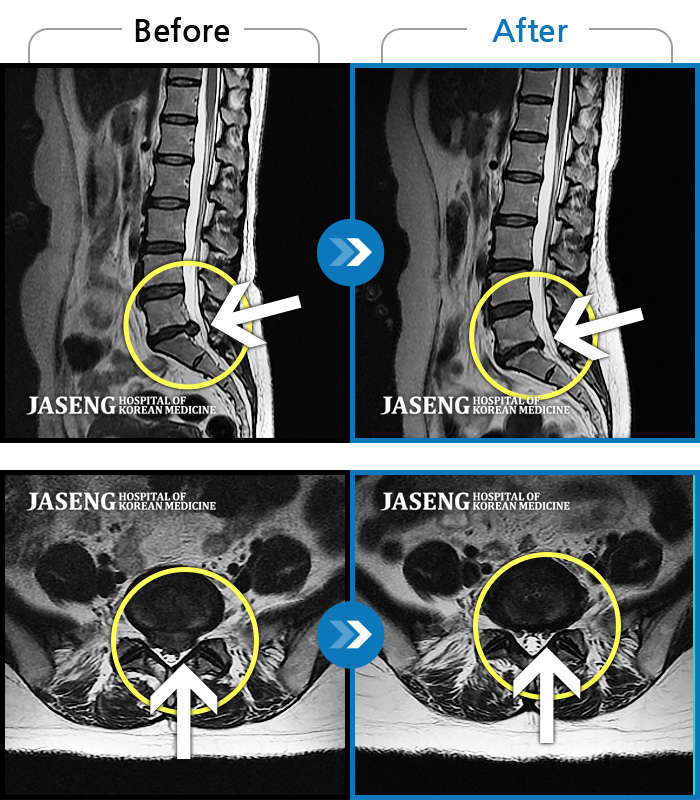

휴직중 허리디스크로 걷지도 못하고 정형외과에서 전부 수술을 권유하는 저에게 비수술로 희망을 주셨어요~^^

지금도 통증이 있으면 통원을 가는데 갈때마다 한결 같으신 원장님 추천합니다~^^